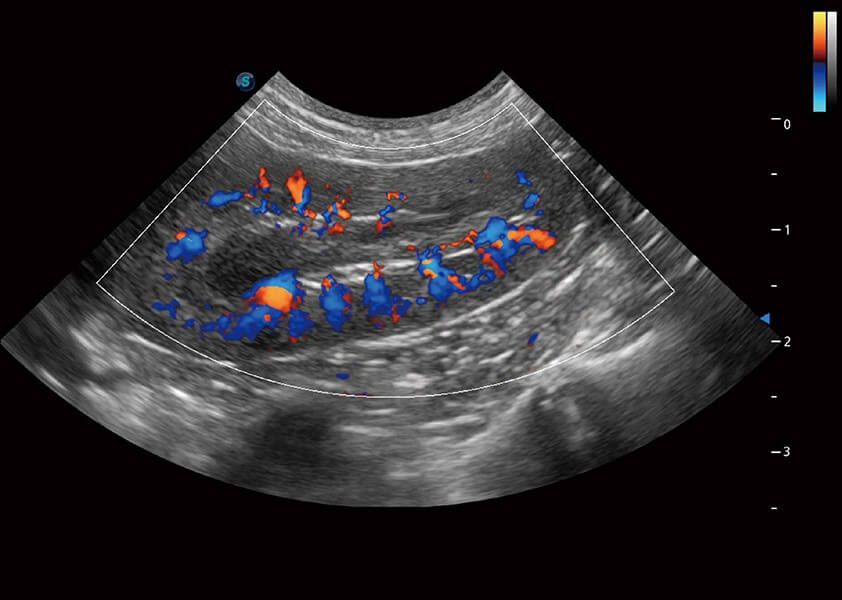

Micro F 显微血流成像

通过创新的Matrix E自适应滤波器和超长时间域算法,极大提升超低速微细血流的检出能力,同时更精准地滤除软组织和噪声信号,为兽用医生提供以往无法通过常规血流获得的疾病诊断信息。

优异的基础图像

(犬)肾脏血流